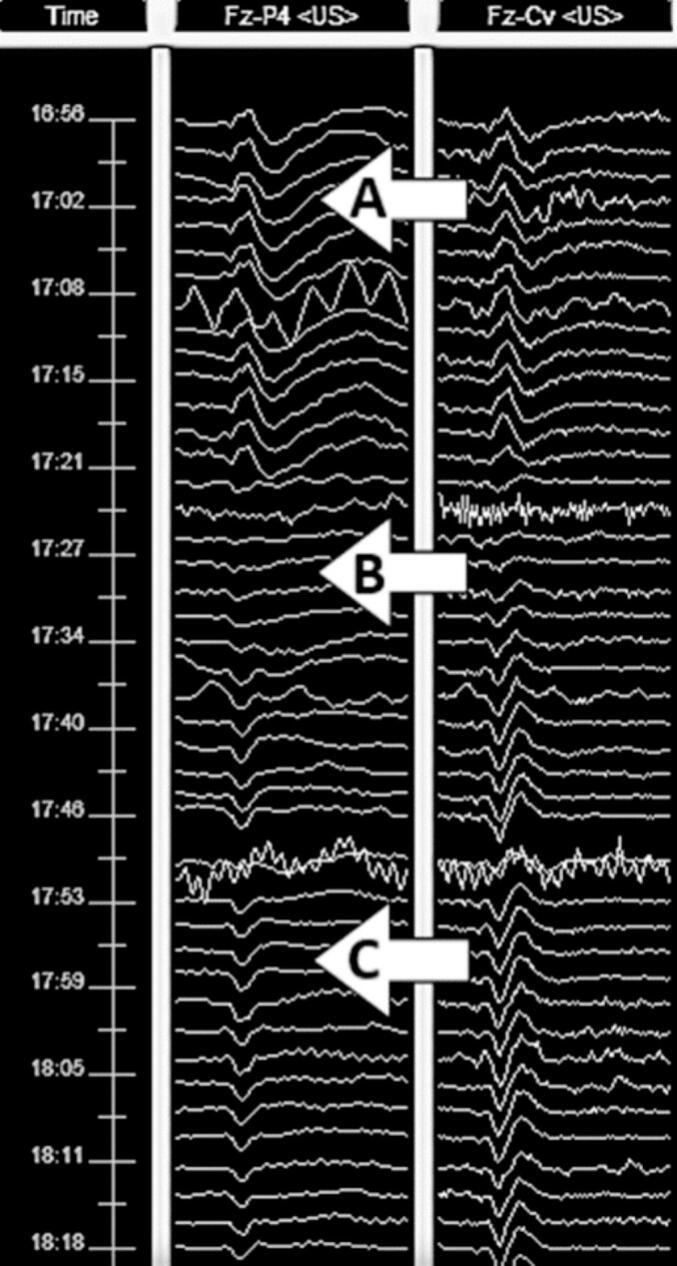

IONM and clinical data from 273 patients who underwent craniotomy for aneurysm clipping from 2019 until 2021 were retrospectively reviewed. Significant IONM changes and POD were respectively evaluated based on visual review of data and clinical documentation. POD was assessed multiple times in the ICU using the Intensive Care Delirium Screening Checklist (ICDSC).

Of the 273 patients undergoing craniotomy with IONM, 83 had POD (30.4 %). Significant IONM changes were noted in 42 patients, of which 19 patients had POD (45.2 %). In contrast, 231 patients had no IONM changes during surgery, of which 64 (27.7 %) patients had POD. Multivariable analysis showed that significant IONM changes were associated with POD, OR: 2.09 (95 % CI 1.01–4.43, p-value: 0.046). Additionally, somatosensory evoked potentials (SSEP) changes were significantly associated with POD (p-value: 0.044).

Significant IONM changes are associated with an increased risk of POD in patients undergoing craniotomy for aneurysm clipping. Our findings offer a strong basis for future research and analysis of EEG and SSEP monitoring to detect and possibly prevent POD.